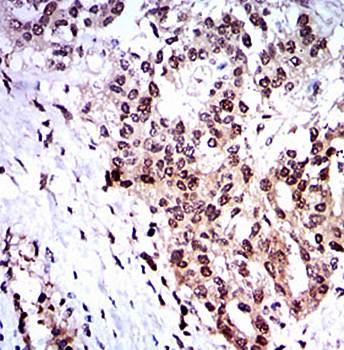

IHC analysis of SKP1 using anti-SKP1 antibody. SKP1 was detected in paraffin-embedded section of human colon cancer tissues. Heat mediated antigen retrieval was performed in citrate buffer (pH6, epitope retrieval solution) for 20 mins. The tissue section was blocked with 10% goat serum. The tissue section was then incubated with 1 µg/ml rabbit anti-SKP1 Antibody overnight at 4°C. Biotinylated goat anti-rabbit IgG was used as secondary antibody and incubated for 30 minutes at 37°C. The tissue section was developed using Strepavidin-Biotin-Complex (SABC) with DAB as the chromogen.